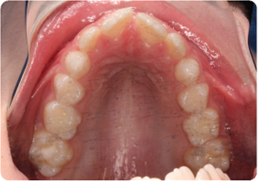

Each case shows the front view and an arch or side view, before and after BioLign Method-guided treatment.

Crowding with irregular gaps resolved into even alignment